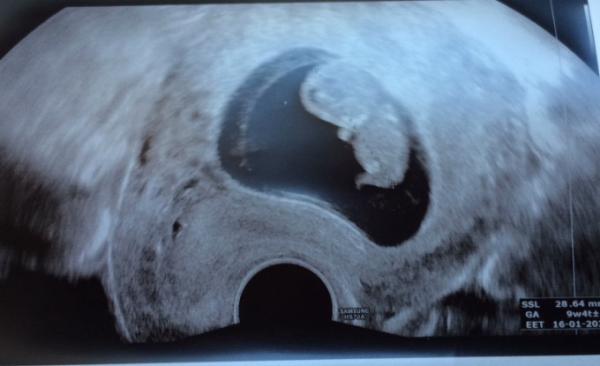

Hallo ihr lieben, ich wollte mal ein neues Bildchen zeigen und erzählen, dass alles gut ist bei mir. Mittlerweile ist das Kleine 28,64mm groß, das Herz schlägt und es hat sich auch fleißig bewegt Ich bin heute 9+4. Anstonsten gebt es mir nicht so gut. Morgens muss ich auf leeren Magen immer ein paar mal würgen, was an sich zwar schon nervig ist, aber seit einigen Tagen platzt mir da immer eine Ader in der Nase auf, sodass ich heute zum Beispiel 1 Stunde und 15 Minuten überm Waschbecken hing und das Blut hab laufen lassen... deshalb muss ich jetzt zum HNO. Und da die nächsten freien Termine erst ab August sind und ich da hoffentlich mit der morgendlichen Übelkeit und dem Würgen/Erbrechen durch bin lohnt sich dann kein Termin mehr. Deshalb muss ich mich morgen früh um acht ins Wartezimmer setzen und hoffen dran zu kommen. Ich hoffe einerseits, dass ich nicht allzu lange warten muss und andererseits hoffe ich, dass ich es mit der Übelkeit und eventuellem Nasenbluten überhaupt vernünftig hin schaffe das wird sicher nicht angenehm und einfach werden... vor allem wird mir vom Bus fahren an sich schon oft schlecht, aber zurzeit ist es noch schlimmer. Letzten Mittwoch habe ich mich an der Busendhaltestelle übergeben. Zum Glück habe ich es noch aus dem Bus geschafft.... Naja aber über das Bild zumindest freue ich mich sehr Ich hoffe euch allen geht es gut! Liebe Grüße